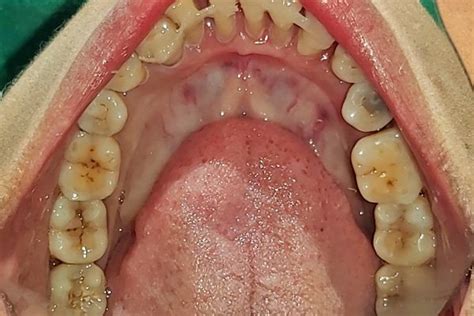

Hemi Sectioned Tooth

Case Report On Tooth Hemisectioning as an Alternative to Extraction ...

A Case report on remarkable healing by secondary intention in a hemi ...

Dental Hemi Section

Hemi Section with Teeth